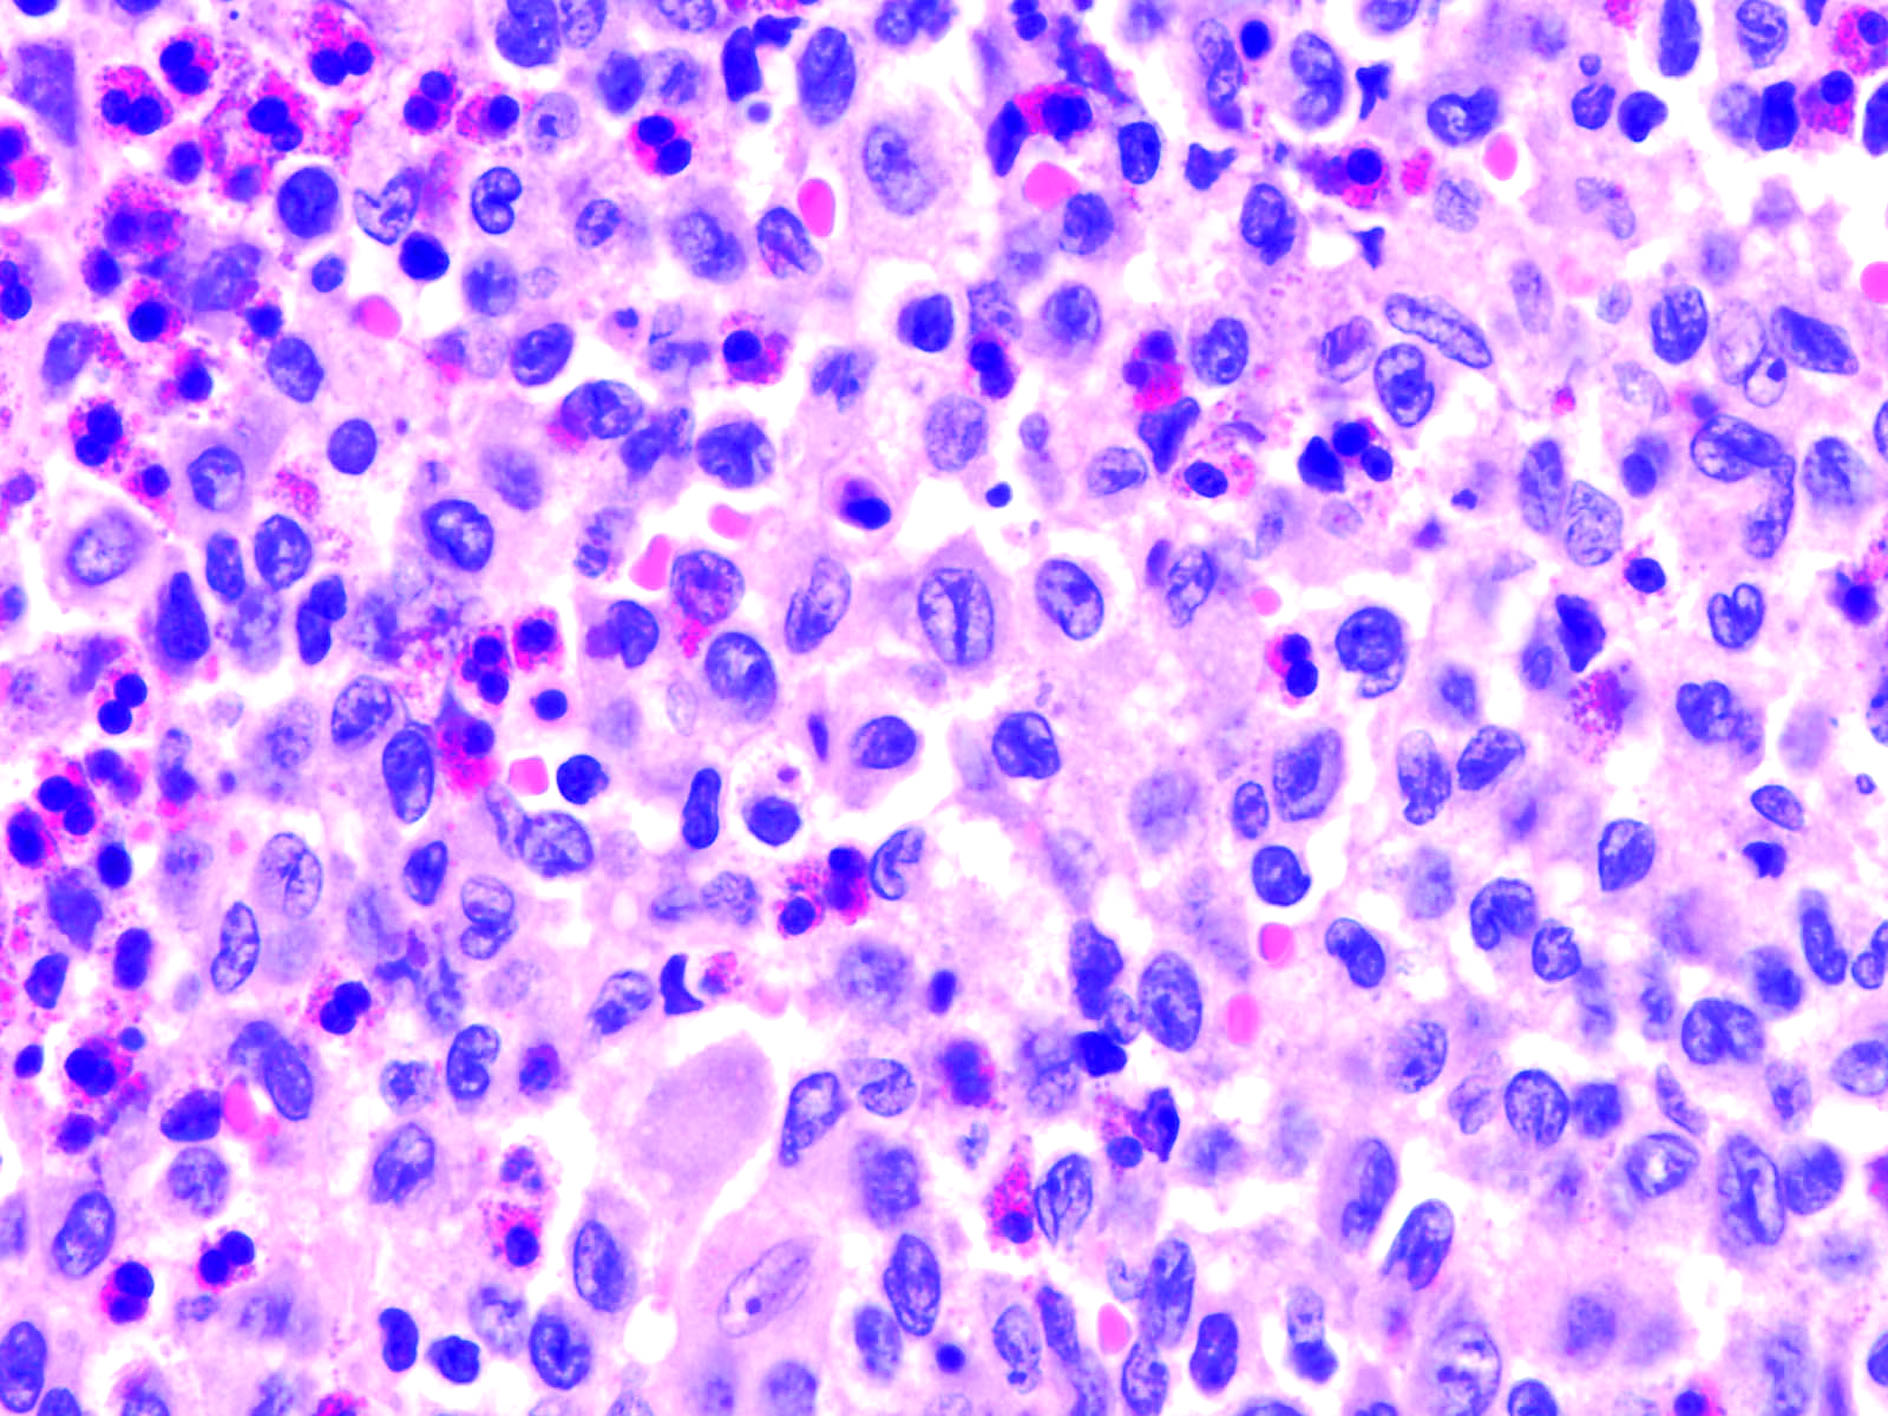

Ενώ οι χαρακτηριστικές αλλοιώσεις της ιστιοκυττάρωσης LCH  είναι κοκκιώματα, κύτταρα Langerhans, μακροφάγα, ηωσινόφιλα, Τ λεμφοκύτταρα και κύτταρα πλάσματος, πιστεύεται ότι η κλωνική επέκταση των ελαττωματικών ανώριμων κυττάρων Langerhans είναι το βασικό παθογενετικό στοιχείο.

Η ιστολογική διάγνωση των βλαβών LCH βασίζεται στη χρώση της πρωτεΐνης S-100 και του αντιγόνου CD1a ή στην εύρεση κοκκίων Birbeck (σε σχήμα ρακέτας του τένις) στο ηλεκτρονικό μικροσκόπιο. Η παθολογοανατομική εξέταση αποκαλύπτει το σχηματισμό κοκκιώματος από ιστιοκύτταρα με μεγάλο μέγεθος και αυλακωτό πυρήνα, χωρίς σημεία κακοήθειας.